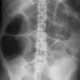

La radiografía simple puede revelar signos de dilatación del esófago, estómago, intestino delgado o colon, que pueden parecerse a una imagen de íleo o una obstrucción mecánica. Estas dilataciones pueden sugerir que existe una obstrucción en el tracto gastrointestinal, pero es importante tener en cuenta que las obstrucciones mecánicas del estómago, el intestino delgado o el colon son mucho más comunes que la gastroparesia o la obstrucción intestinal pseudo-obstructiva. Debido a esto, se deben excluir con procedimientos adicionales, como la endoscopia o la tomografía computarizada (TC) con enterografía, especialmente en pacientes con antecedentes quirúrgicos, inicio reciente de síntomas o dolor abdominal. En estos casos, la evaluación diagnóstica debe centrarse en confirmar si hay una obstrucción mecánica real, ya que el tratamiento para una obstrucción mecánica es muy diferente al de un trastorno funcional como la gastroparesia.